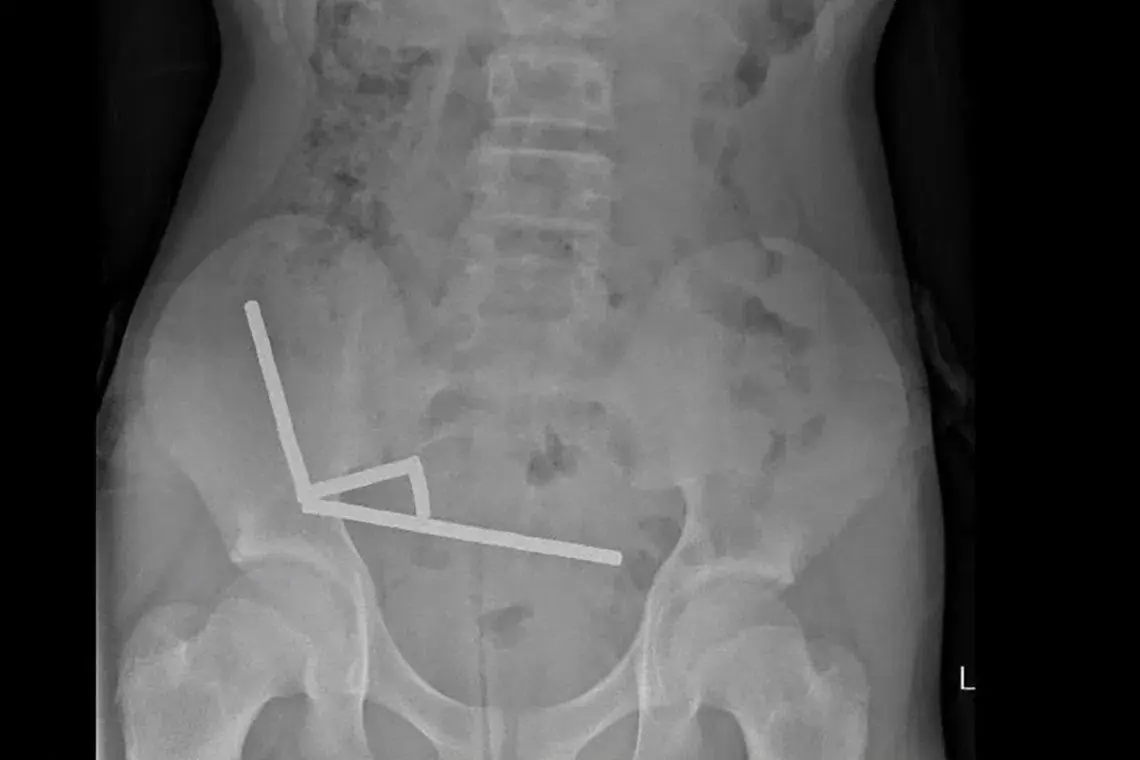

An X-ray showed the magnets had clumped together in four straight lines inside the child’s intestines.

“These appeared to be in separate parts of bowel adhered together due to magnetic forces,” they said.